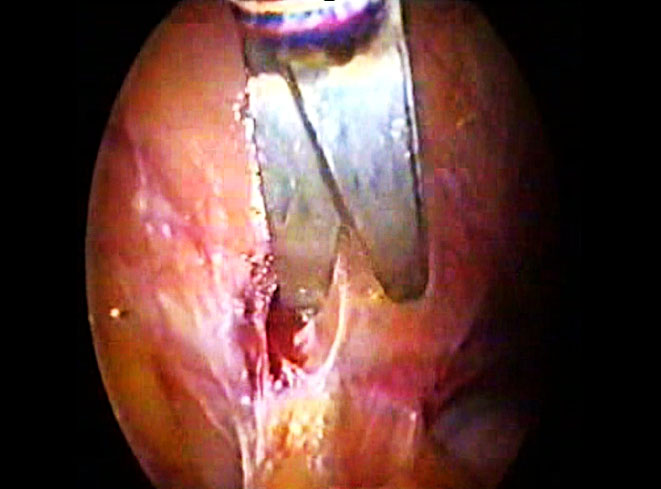

2) Clipping the uterine artery. This should be undertaken early during surgery, either at the origin of the uterine artery (Figure 9) or near its uterine insertion, while carefully safeguarding the ureter. The use of a temporary vascular loop or 'shoelace' technique, which is removed at the end of the procedure, can further assist in minimizing blood loss.13

9

Uterine artery clipped at the origin.